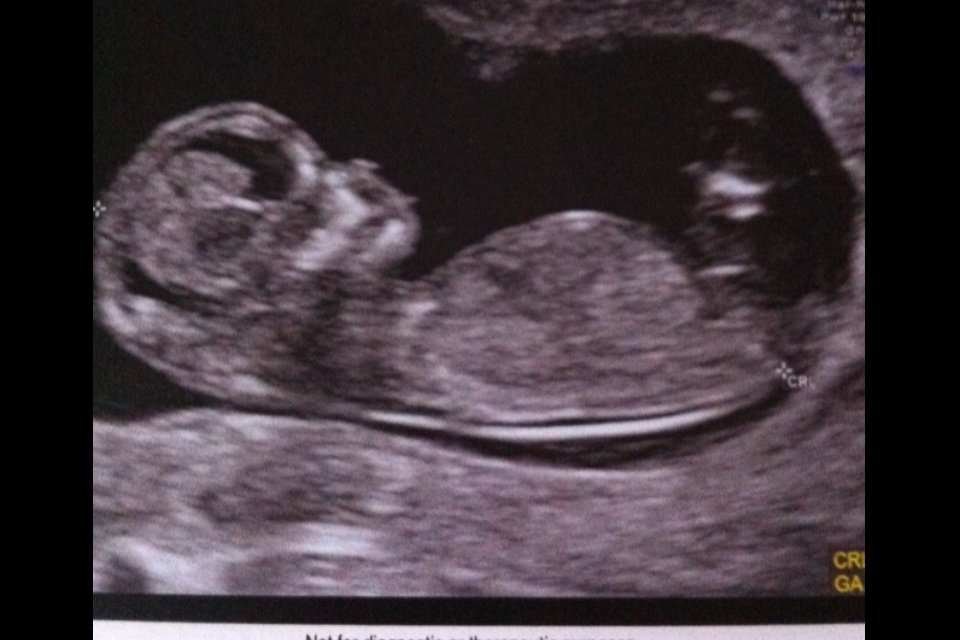

Hmmmm maybe girl....but the possible shadow on top is throwing me a bit and I'm not sure the whole nub is captured....congrats on bub :)

Tentatively guess boy.

Leaning boy

leaning boy too, if the nub is where I see it, it's a difficult one.

I see the shadow too, I cautiously lean boy.

It's a boy